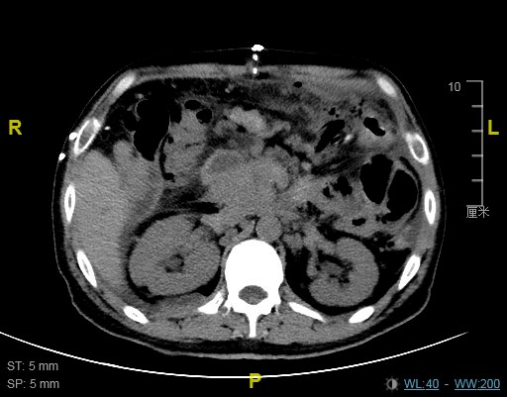

王先生出院前复查CT影像